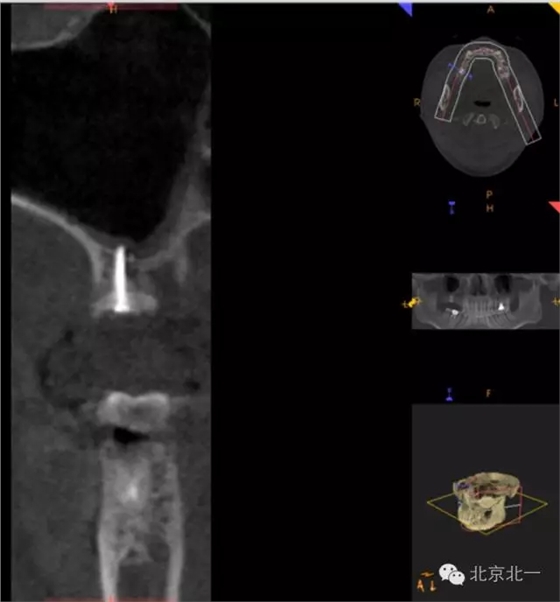

圖十五:備洞

圖十六:植入植體

圖十八:手術前CBCT

圖十九:手術后當天CBCT

圖二十-二十二:ONLAY植骨半年后